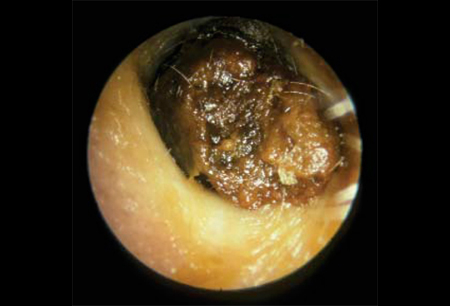

cerumen impaction

impacted ear wax

decreased hearing

Can be caused by hearing aid use, narrow ear canals, cotton swab use

Treatment: removal with suction or curette